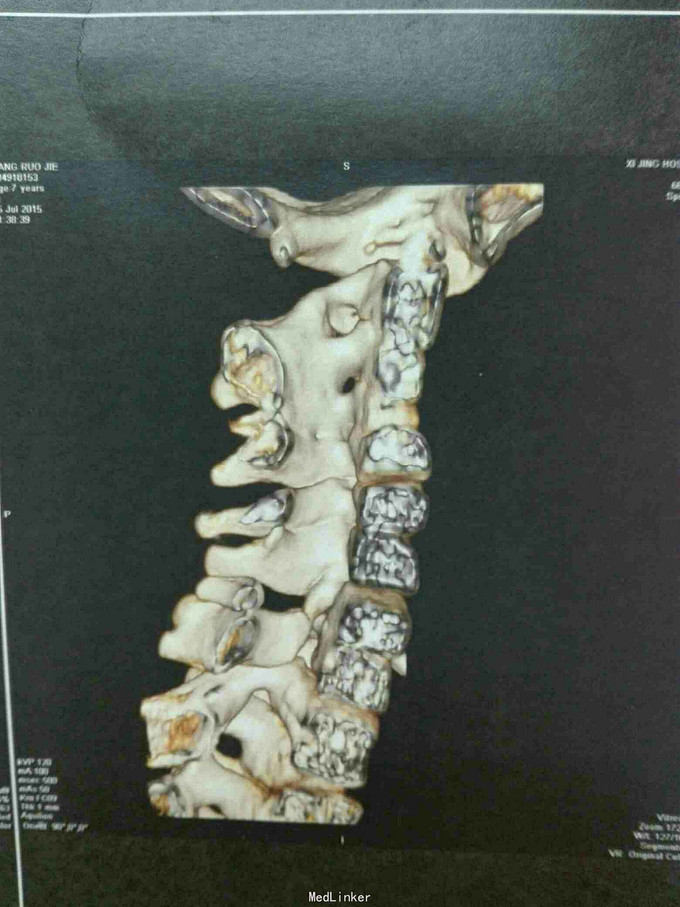

先天脊柱畸形

先天脊柱畸形8年。

严重脊柱畸形病例

先天性脊柱侧凸畸形

脊柱先天畸形